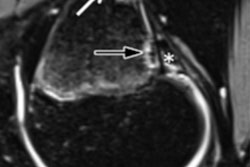

However, the researchers found significantly reduced cerebral blood flow one year later, with an average decrease of 10 mL/100 g of blood per minute compared with healthy controls. Interestingly, cerebral blood flow was normal when the athletes returned to play. MR images also indicated increasing significant elevations in mean diffusivity. The elevations were primarily in the posterior and superior corona radiata from the early symptomatic phase of the concussion through the return to play and one year later, which could indicate edema in that brain region.